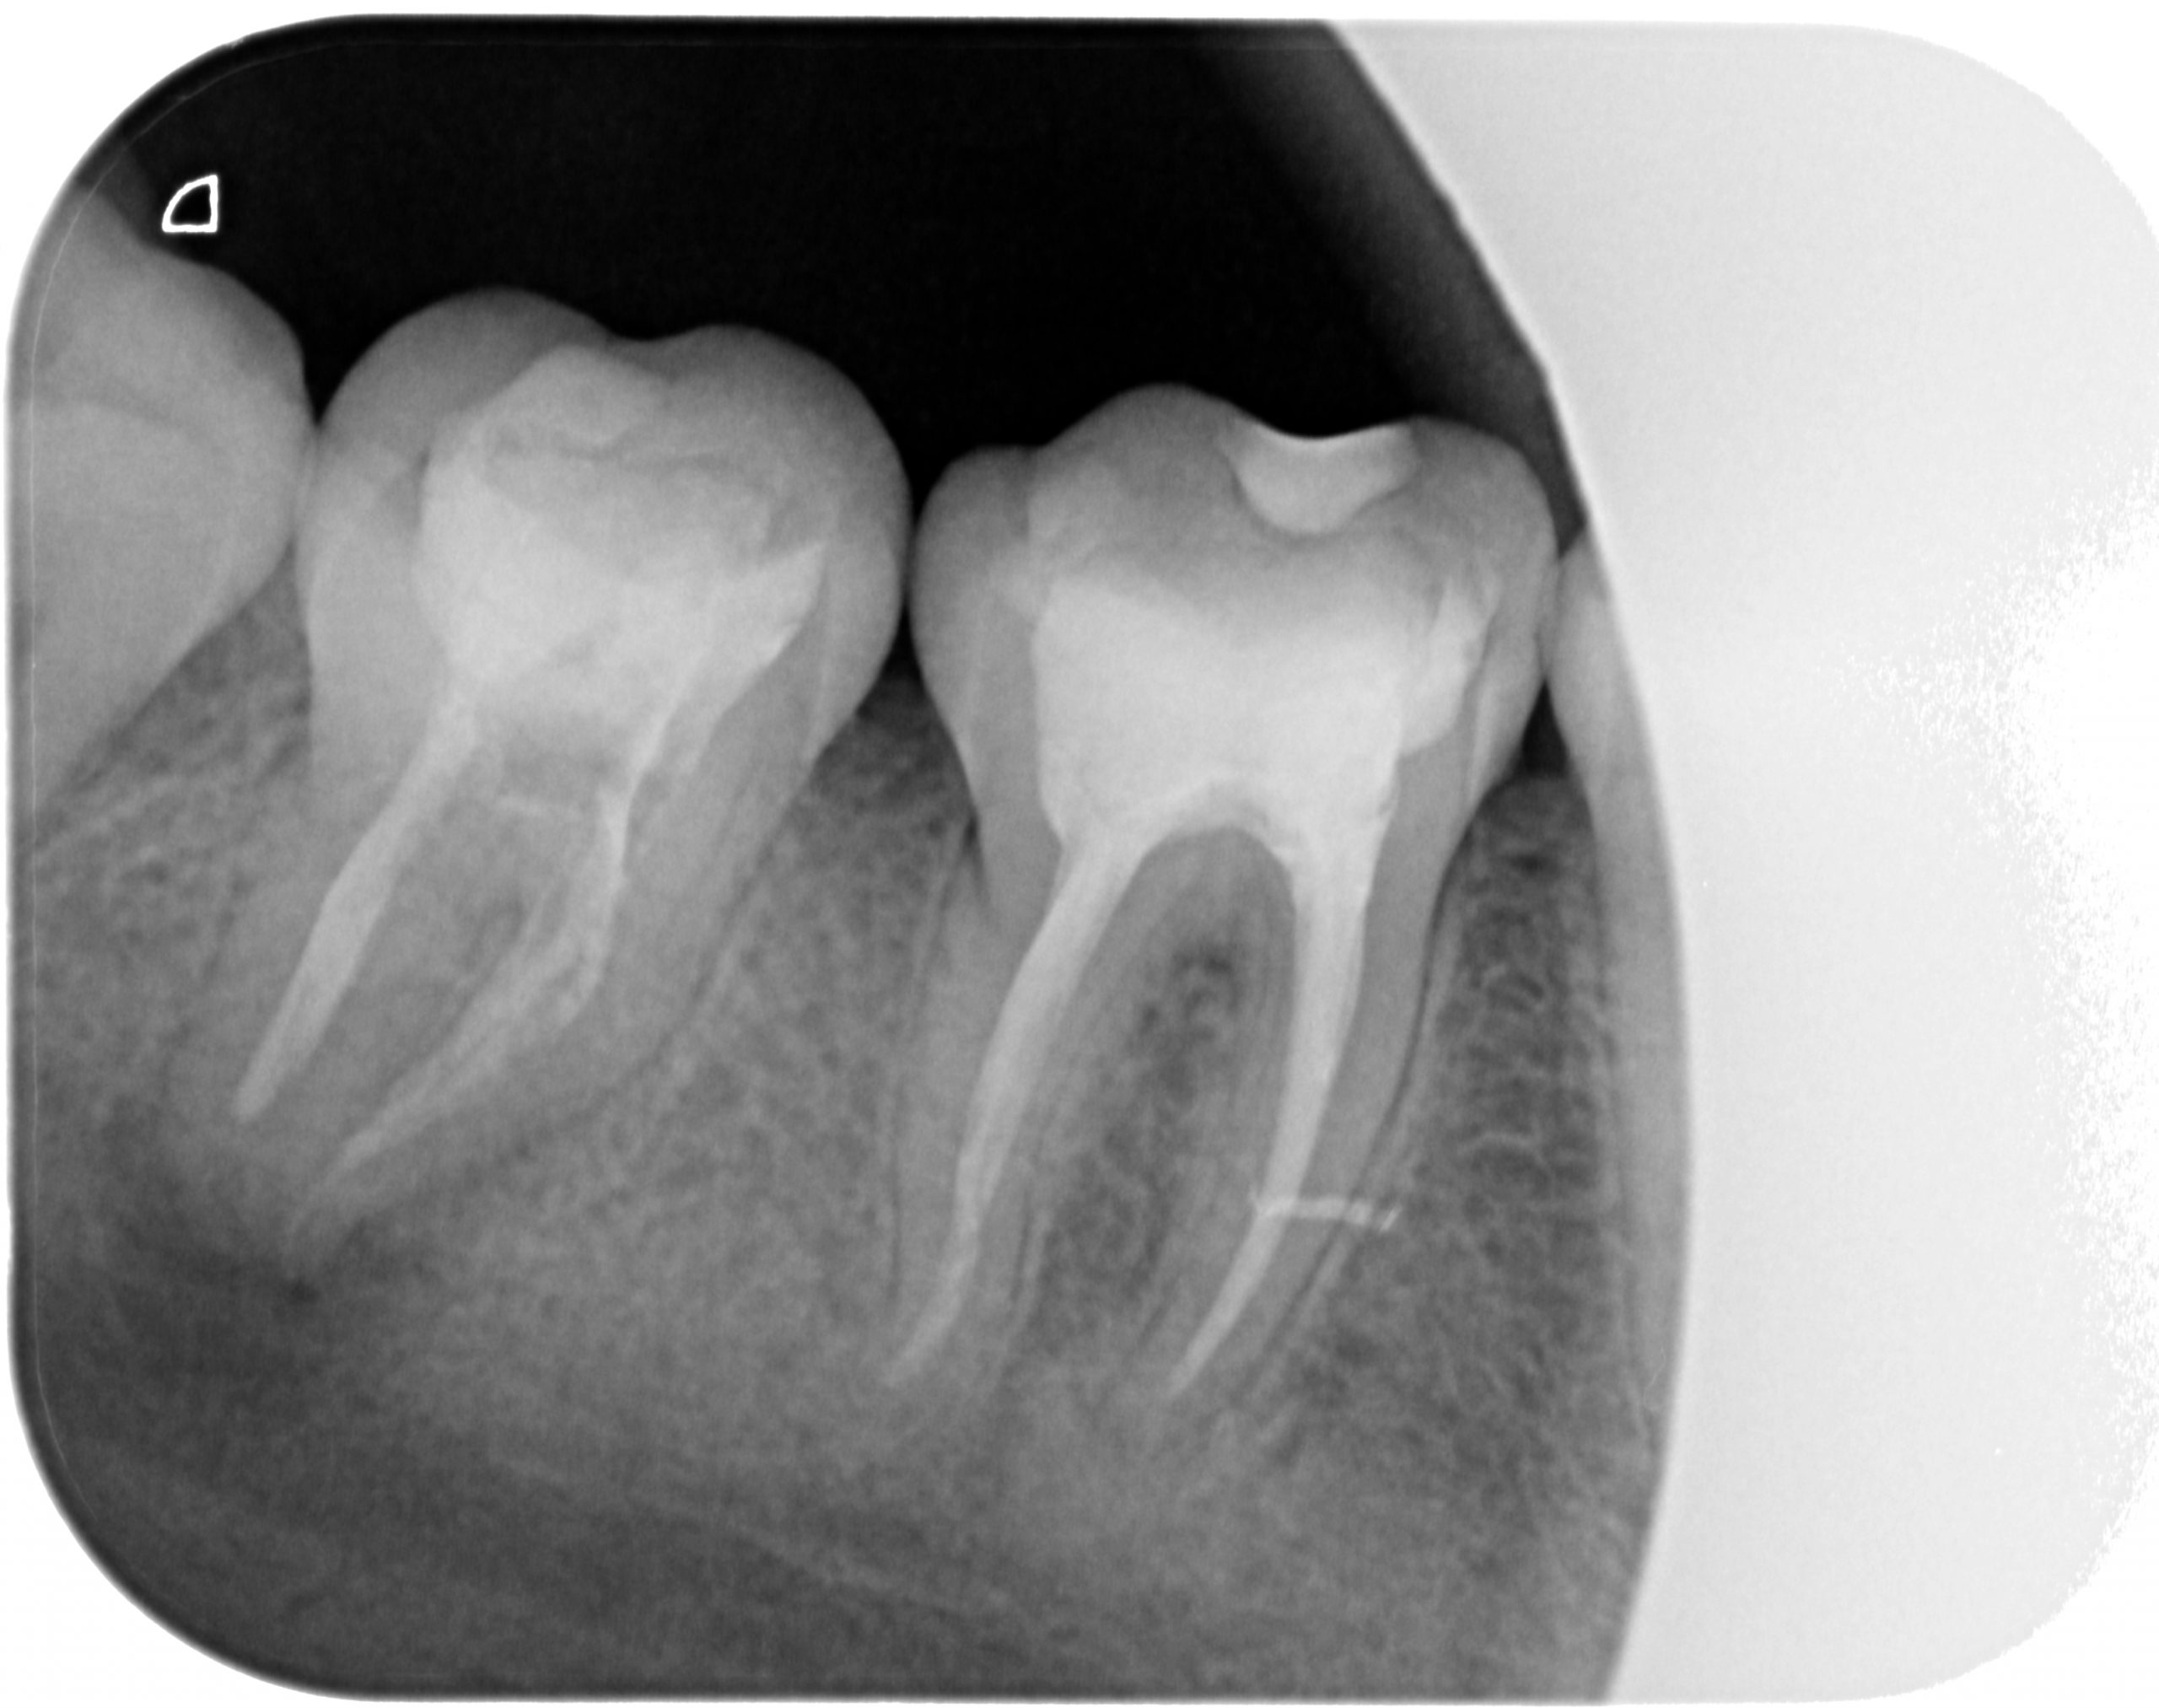

RX Inicial:

RX control 6 meses:

Rx final: